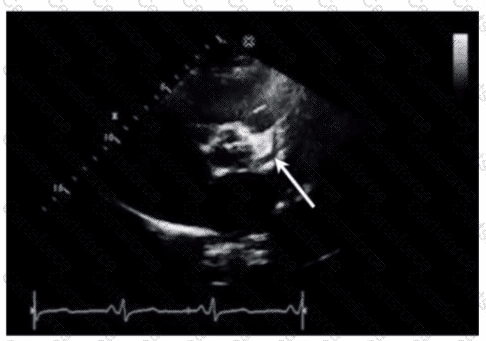

Which coronary artery is identified by the arrow on this image?